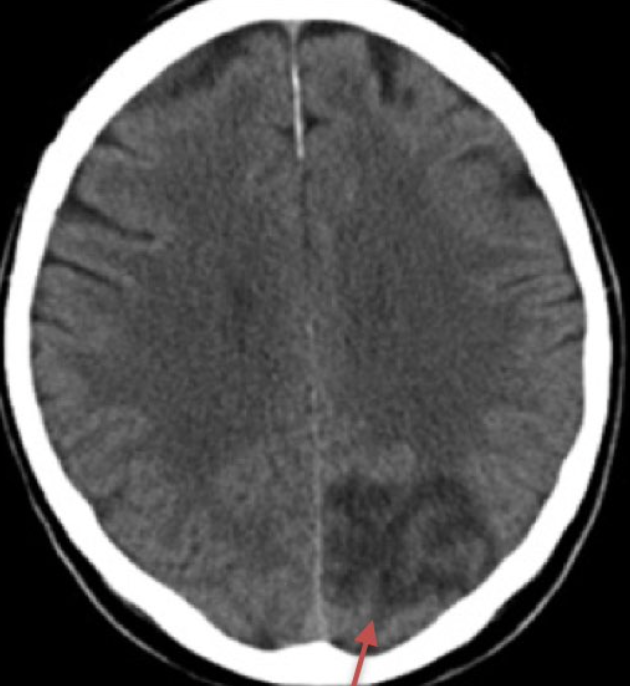

epidural haematoma

subarachnoid haemorrhage

subdural haematoma

infarct